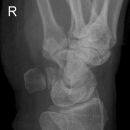

Scaphoid-Quartett

Dringender Verdacht auf Scaphoidfraktur (2) bei zweifelhaften Befund in den Standardprojektionen.Notwendigkeit fraglich, da bei klinischen Verdacht und zweifelhaften Röntgenbefund in den Standardaufnahmen des Handgelenks ohnehin die Ruhigstellung indiziert ist, so dass sich eine weiterführende Diagnostik zunächst erübrigt. Ist auch die Kontrolluntersuchung nicht eindeutig, so sind CT oder Szintigraphie in ihrer Aussage zuverlässiger als die Spezialprojektionen.

Scaphoidfrakturen: 70% der Frakturen der Handwurzel sind Scaphoidfrakturen. 2/3 sind im mittleren Drittel. Meist Querfrakturen.

Dehizenz > 1mm -> instabil -> Gefahr Pseudarthrose.

Cave: Begleitverletzungen: Proc. syloideus radii, Lunatum, Capitatum, SL-Dissoziation, perilunäre Dissoziaton, DeQuervain Luxationsfraktur.